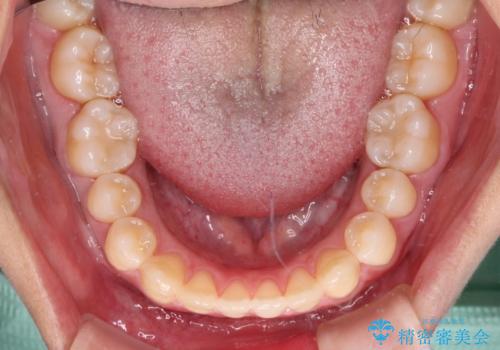

隙間だらけの歯列 インビザラインで改善

- 前歯の上下スペースと前歯の隙間を気にして来院された患者様です。

飲み込みや話をするときに舌を突出させる癖が強くあり、それが原因でスペースが空いていました。

舌癖を改善するためのトレーニングを行いながら、インビザラインにより上下の前歯の隙間を閉じていくこととしました。